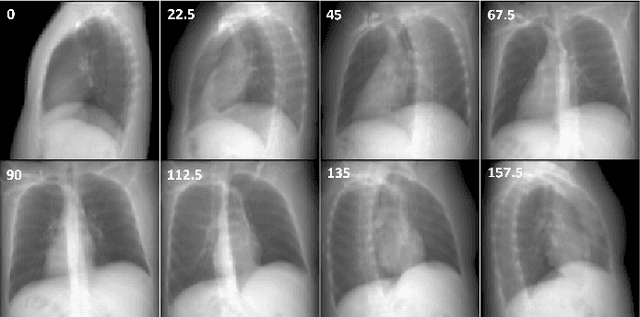

Abstract:Computed Tomography (CT) scans are the standard-of-care for the visualization and diagnosis of many clinical ailments, and are needed for the treatment planning of external beam radiotherapy. Unfortunately, the availability of CT scanners in low- and mid-resource settings is highly variable. Planar x-ray radiography units, in comparison, are far more prevalent, but can only provide limited 2D observations of the 3D anatomy. In this work we propose DIFR3CT, a 3D latent diffusion model, that can generate a distribution of plausible CT volumes from one or few (<10) planar x-ray observations. DIFR3CT works by fusing 2D features from each x-ray into a joint 3D space, and performing diffusion conditioned on these fused features in a low-dimensional latent space. We conduct extensive experiments demonstrating that DIFR3CT is better than recent sparse CT reconstruction baselines in terms of standard pixel-level (PSNR, SSIM) on both the public LIDC and in-house post-mastectomy CT datasets. We also show that DIFR3CT supports uncertainty quantification via Monte Carlo sampling, which provides an opportunity to measure reconstruction reliability. Finally, we perform a preliminary pilot study evaluating DIFR3CT for automated breast radiotherapy contouring and planning -- and demonstrate promising feasibility. Our code is available at https://github.com/yransun/DIFR3CT.